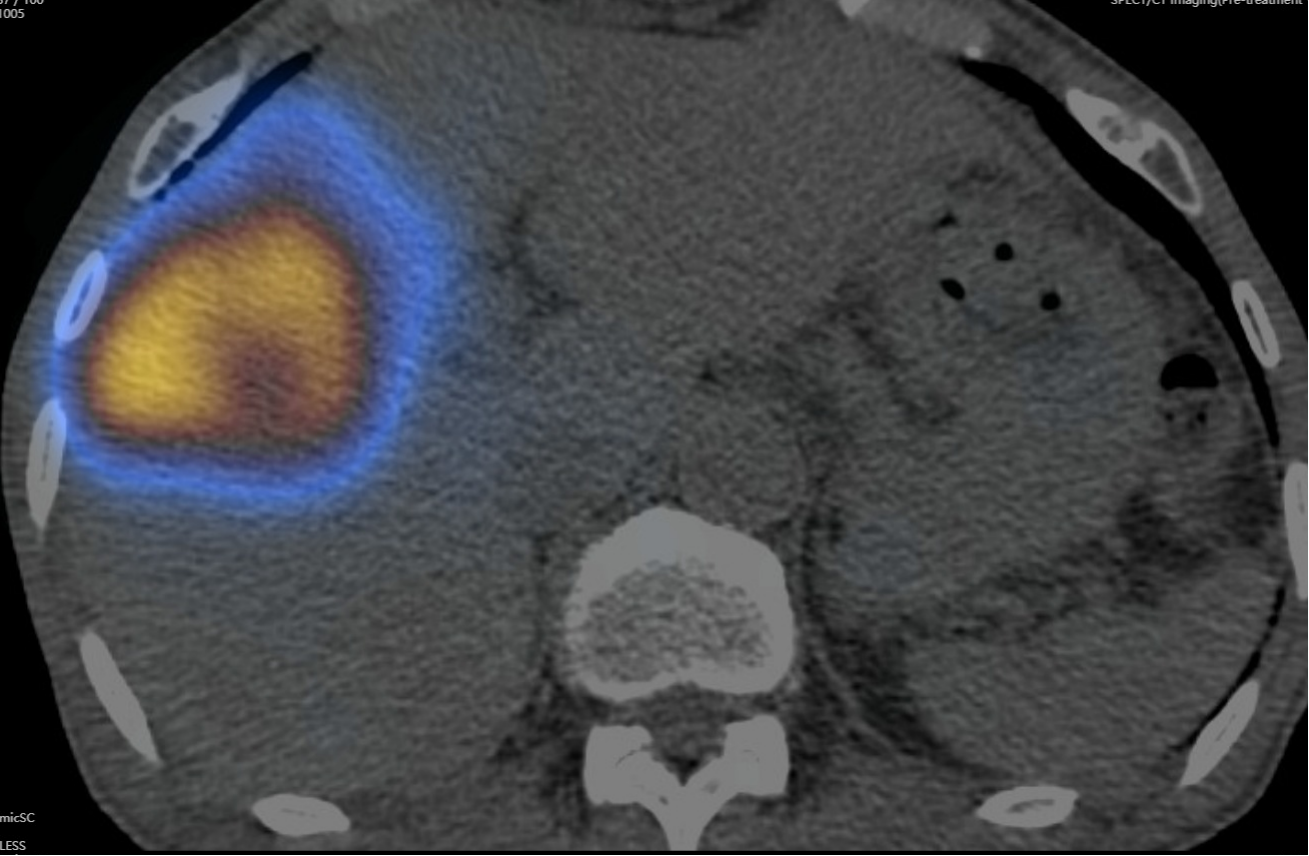

据介绍,患者三个月前体检发现肝脏占位,经钇[90Y]MDT初步评估,考虑患者肝脏肿瘤较大,且合并门静脉癌栓、肝硬化,建议先行钇[90Y]微球介入治疗进行降期转化,再考虑手术切除。患者经介入血管评估及SPECT/CT检查后,结果显示适合行钇[90Y]微球治疗。

患者术后SPECT/CT显示,核素在病灶区沉积良好

术前及术中,疾控感控办公室协助全面做好接诊空间疫情防控和消杀部署,核医学科、放射科、钇[90Y]中心导管室、留观室、肝胆胰中心医护团队严密防护,历时约四小时顺利完成手术。患者术后SPECT/CT显示病灶部位微球浓聚良好,无肝外微球异常浓聚,患者肝功正常,术后第二日顺利出院。